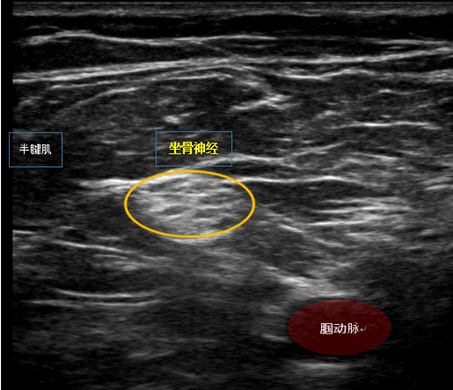

近日,徐州市礦山醫(yī)院麻醉科團(tuán)隊(duì)在鄭蓓主任的帶領(lǐng)下,成功為一名95歲高齡患者實(shí)施了超聲引導(dǎo)下腘窩上坐骨神經(jīng)阻滯麻醉。

在超聲引導(dǎo)下清晰分辨針尖位置,避免誤傷周圍的血管神經(jīng)。并且可將局麻藥物精準(zhǔn)的注射到神經(jīng)周圍,防止鞘內(nèi)注射,使神經(jīng)阻滯更高效、安全。手術(shù)時(shí)長約1小時(shí),術(shù)中予患者右美托咪定持續(xù)靜脈泵注,患者生命體征平穩(wěn)。術(shù)畢患者意識(shí)清醒,安返病房。